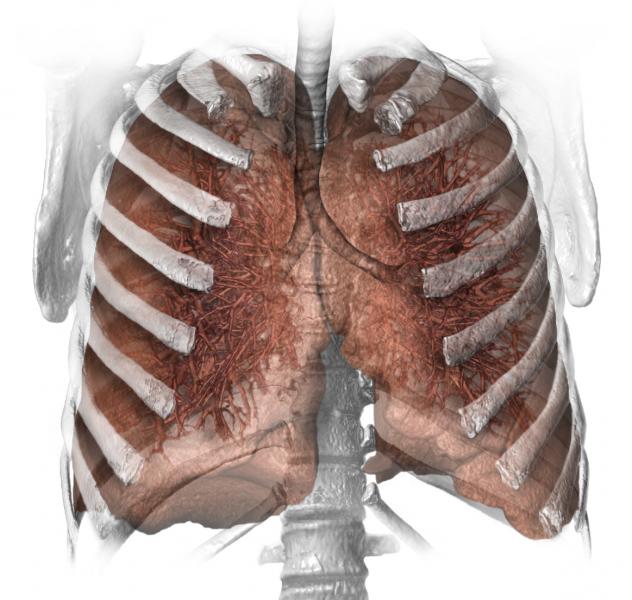

A decline in smoking rates may mean that many people who could have benefited from early detection of lung cancer are dying because they don’t qualify for low-dose computed tomography (CT) scans, according to a group of Mayo Clinic researchers. Their research appears in the Feb. 24 issue of JAMA, the journal of the American Medical Association.